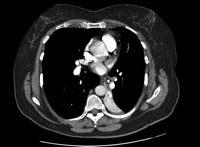

Foreign body aspiration

CT of the chest with intravenous contrast material, showing complete left lower lobe collapse with a radio-opaque object within the left lower main bronchus surrounded by a halo of air

BMJ Case Reports 2008 (doi:10.1136/bcr.06.2008.0013). Copyright 2008 BMJ Group Ltd